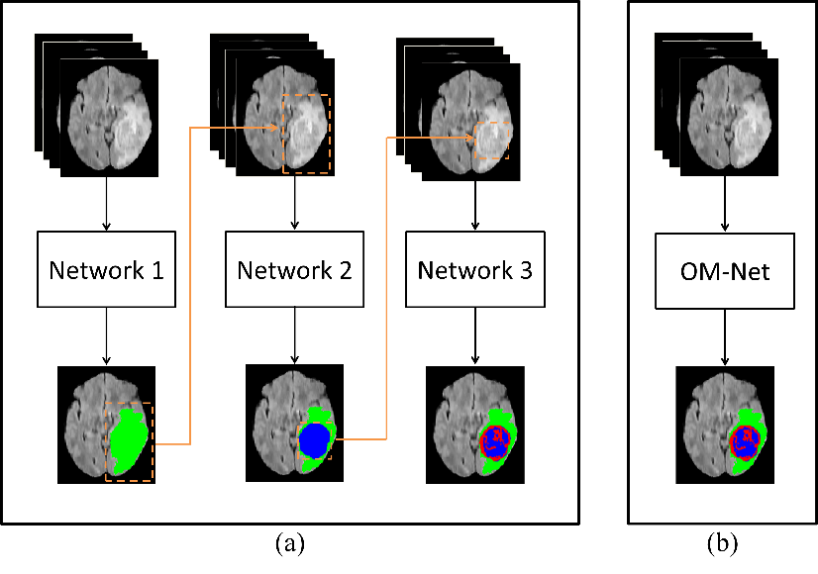

该论文提出了一种新颖的单阶段多任务学习模型,旨在解决脑肿瘤分割任务中最具挑战性的类别不平衡问题。已有工作多采用级联模型策略,通过训练多个单独的深度模型完成由粗到精的分割;然而,该策略会导致系统计算复杂度显著增加,并忽视了模型之间的相关性。为了克服以上不足,丁长兴研究员团队提出了一种端到端的轻量级深度模型,命名为One-Pass Multi-Task Network(OM-Net,见图1)。OM-Net将多个分割任务整合到一个深度模型中,该模型由共享的主干模型和应用于特定分割任务的三个分支构成,分别学习任务间的联合特征和特定任务的判别特征。该论文还提出了跨任务引导的注意力机制,基于前一个任务提供的预测结果,获取目标类别的统计信息并产生通道注意力系数,为当前任务实现更精细的特征校正,并最终提升分割性能(图2)。

图1: (a) 传统级联模型分割框架,使用三个独立网络、以由粗到精的策略分割肿瘤区域;(b) 该获奖论文提出的One-Pass Multi-Task Network(OM-Net)是一种新颖的端到端深度模型,利用任务间的相关性,使用单阶段计算就得到了精确的分割结果,显著降低了模型复杂度。